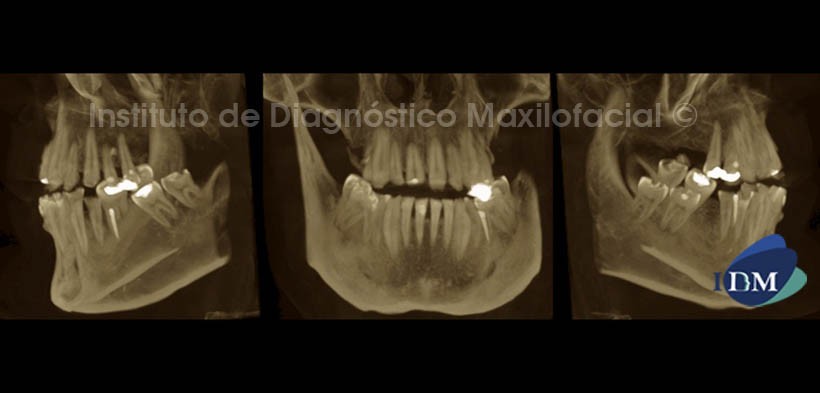

En la reconstrucción tridimensional (Fig. 5) en proyección de máxima intensidad (MIP), se evidencia la perdida de altura dentaria, además de la marcada disminución del esmalte también en caras interproximales presentadose diastemas.